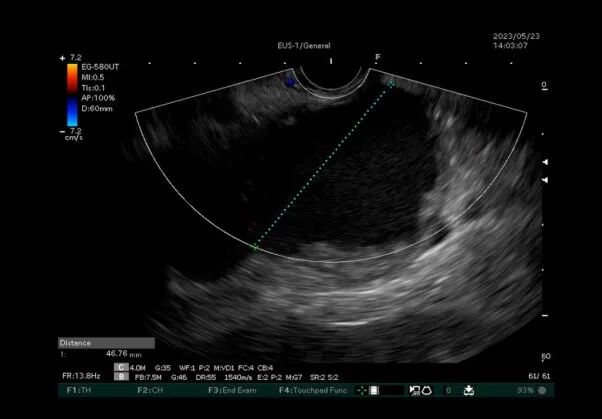

近日我院嘉定院区消化内科胡冰主任、吴军副主任带领的团队,成功为一名胰腺假性囊肿患者,实施精准囊肿引流并放置金属支架。这也是我院首例经超声内镜下电切引流支架置入术(HOT AXIOS技术)。 胡冰教授团队经超声内镜仔细评估后,发现患者囊腔内坏死组织多,传统引流方式效果可能不佳。经过缜密的术前讨论,最终决定采用最新超声内镜下微创电切引流支架置入术(HOT AXIOS技术)。 吴军医生指出: 相较于外科手术和经皮穿刺引流,超声内镜引导下胰腺假性囊肿引流术更加直接方便,相当于在囊肿和胃腔之间搭一个“桥”,把囊肿里面的液体引流到胃腔,一段时间后囊肿就会消失。急性胰腺炎后出现胰腺假性囊肿

本例患者采用的新型胰腺假性囊肿引流技术